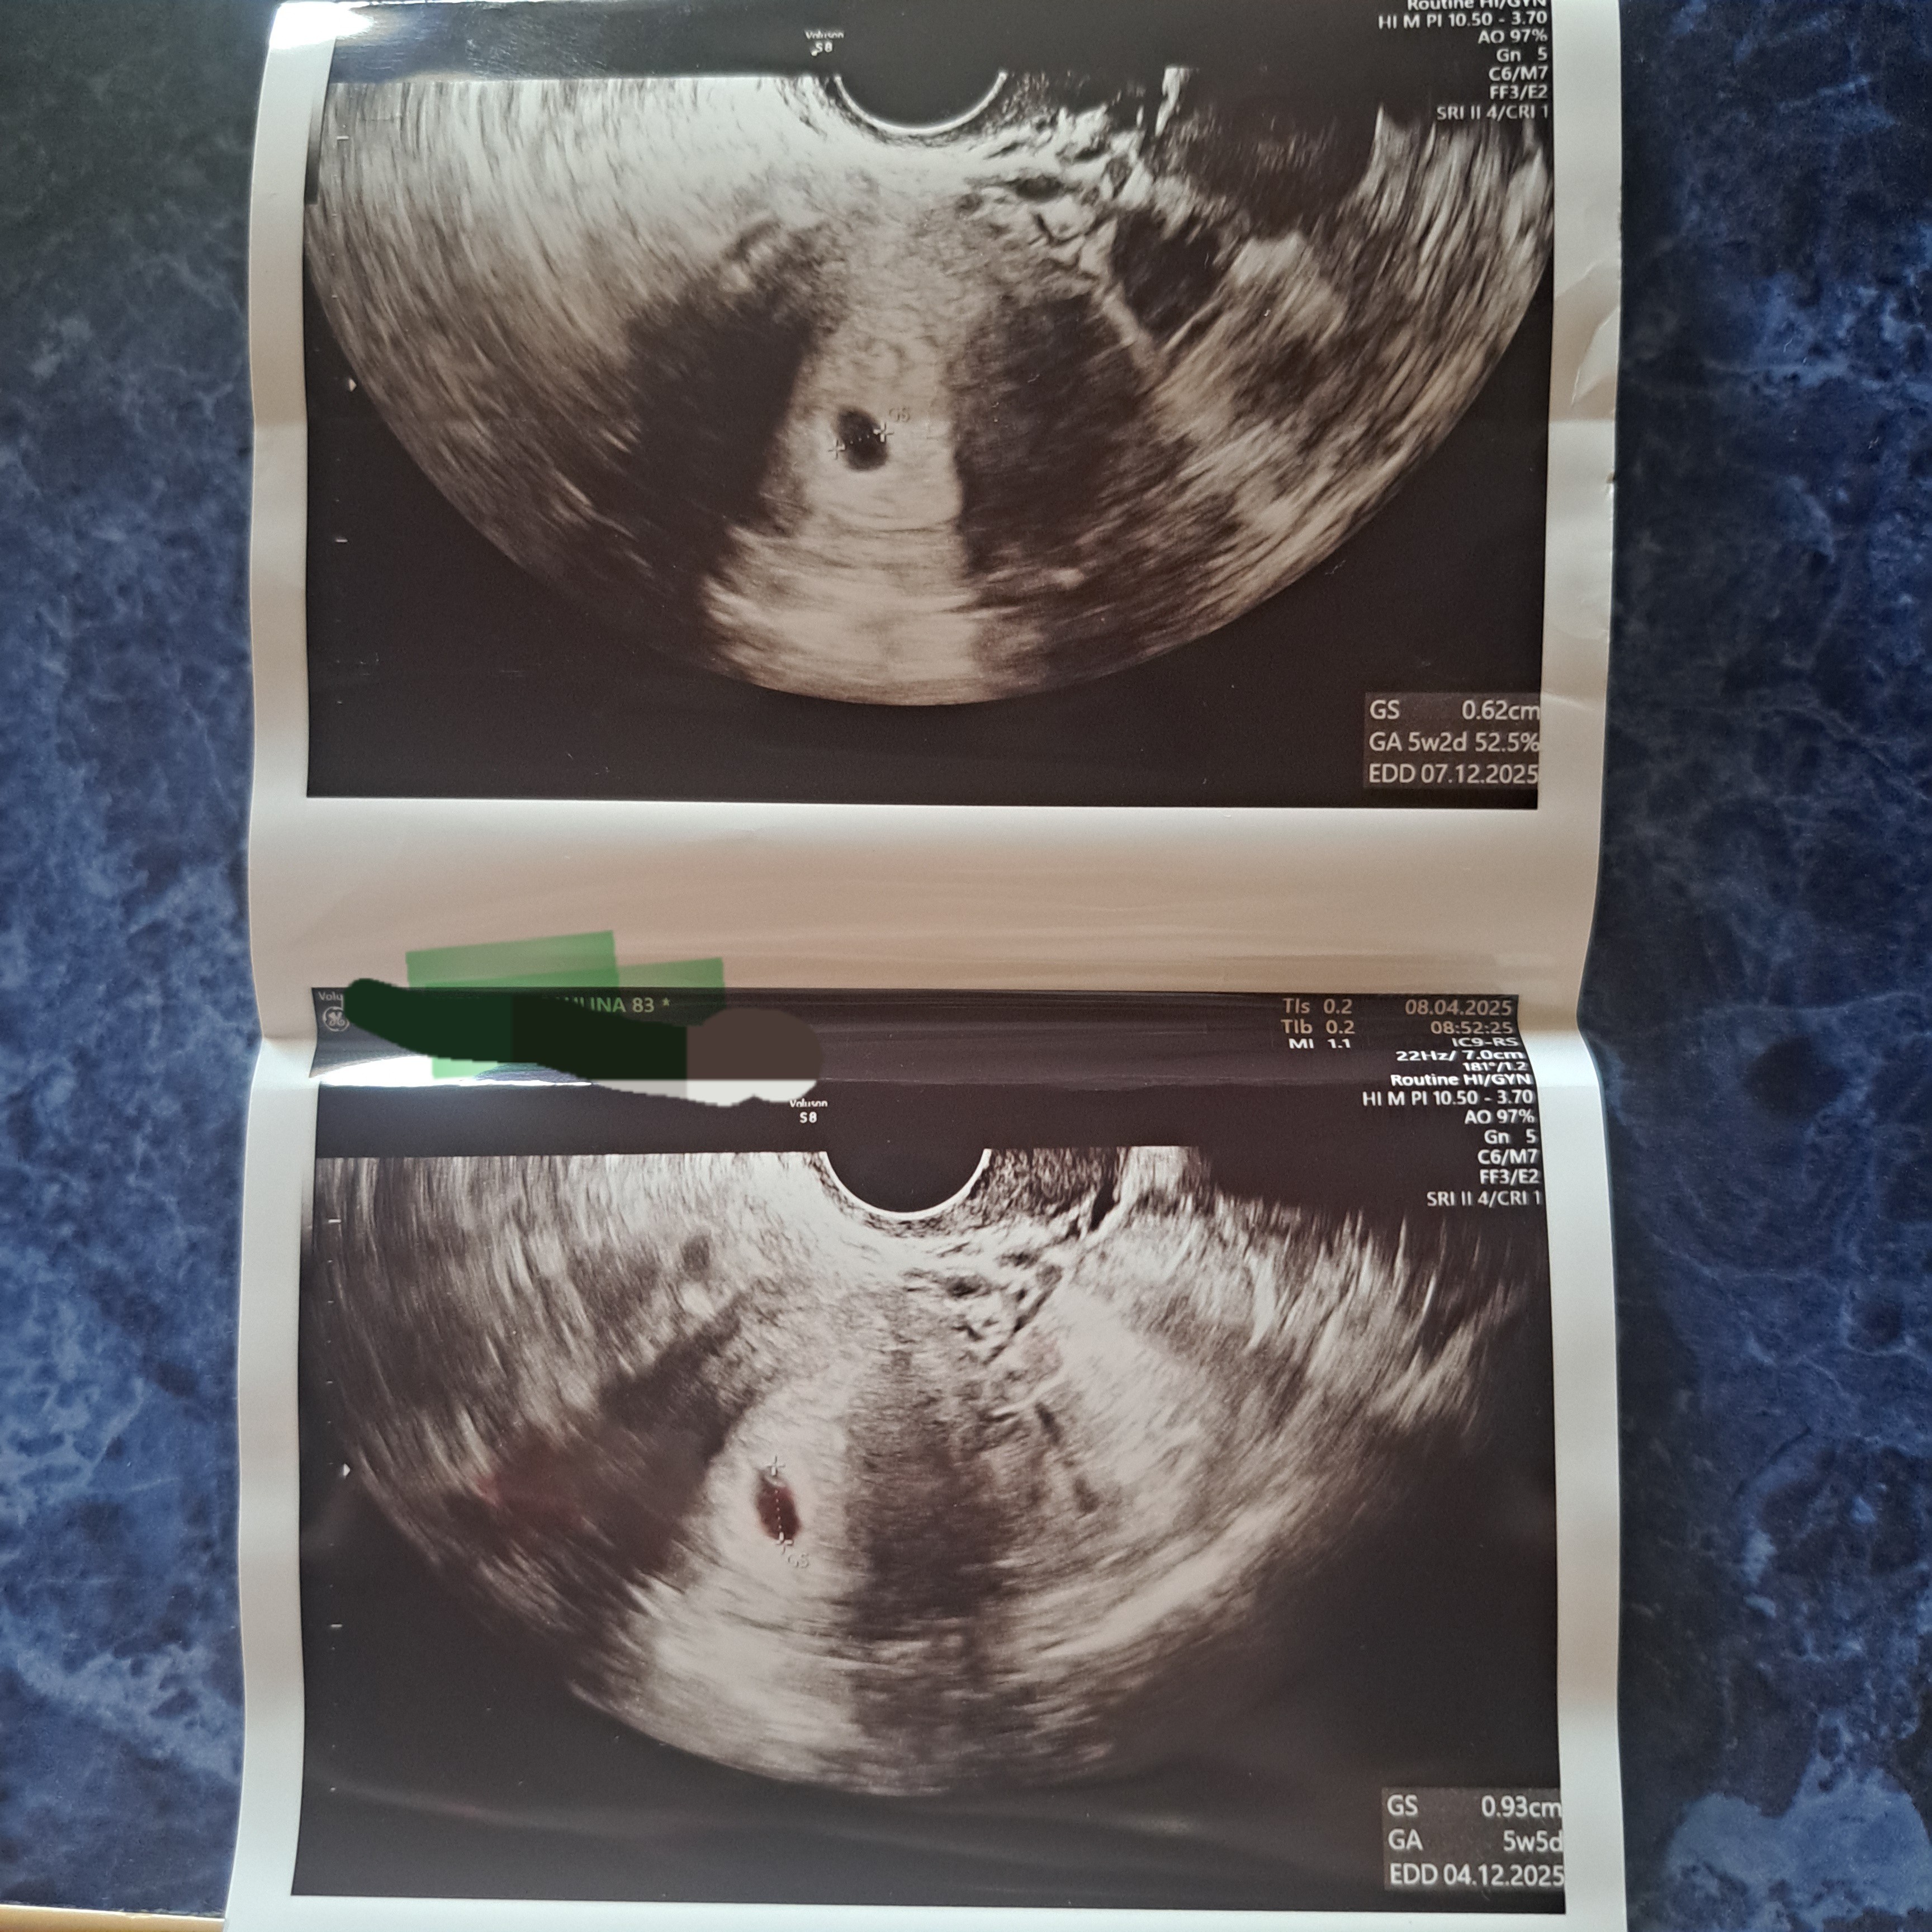

Dziewczyny tak wygląda Moje usg

Pierwsze z5

Drugie z dzis

Wiem że raczej nic z tego nie będzie...

Mam czekać do następnej wizyty .

Wtedy się wszystko wyjaśni

Powinno być już serce bo to 7 ty.

Raczej nastapi poronienie ale twierdzi że ciąża to nie matematyka.

Może w piątek uda mi się dostać do innego ginekologa.

Ciężko określić bo mam nieregularne miesiączki, ostatnia miesiączka 27 luty, więc wypada 7 tydzień, według lekarza to około 5 tydzień, przez to mam przyjść za 2 tygodnie, jutro zrobię Bete.